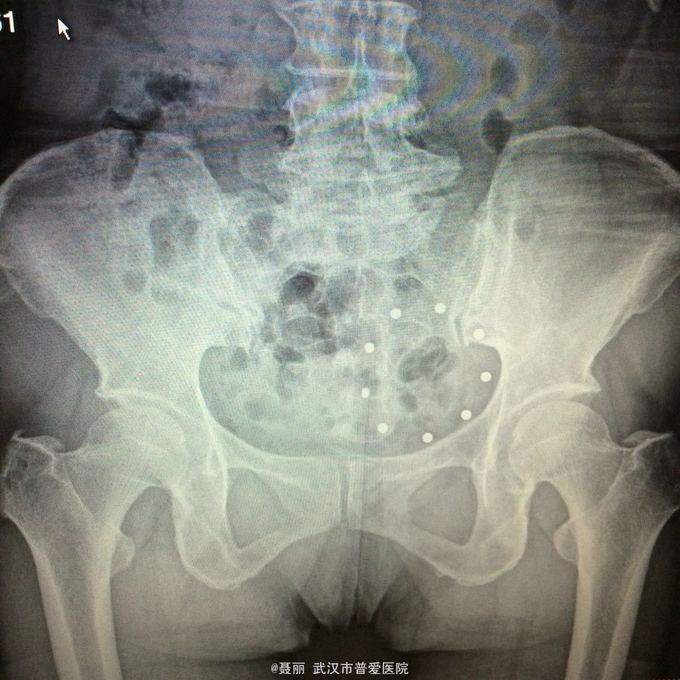

入院诊断:、腰椎滑脱(L4/5 峡部裂性) 诊疗计划:1:完善有关检查2卧床休息,行改善微循环、3.腰椎后路复位减压植骨融合术

行改善微循环、3.腰椎后路复位减压植骨融合术 腰椎滑脱(L4/5 Ⅱ度)、腰椎管狭窄症(L3/4)、腰椎间盘突出症(L5/S1)查体双下肢感觉、活动无明显异常。双下肢末梢血液循环可。换药见伤口对合良好,无明显红肿渗出。伤口已拆线。嘱加强双下肢活动及功能锻炼,避免下肢深静脉血栓,主动及被动四肢活动,预防血静脉及床褥形成,加强腰背肌锻炼,适量康复功能锻炼。一个月后来复查伤口愈合好,疼痛没有,活动可